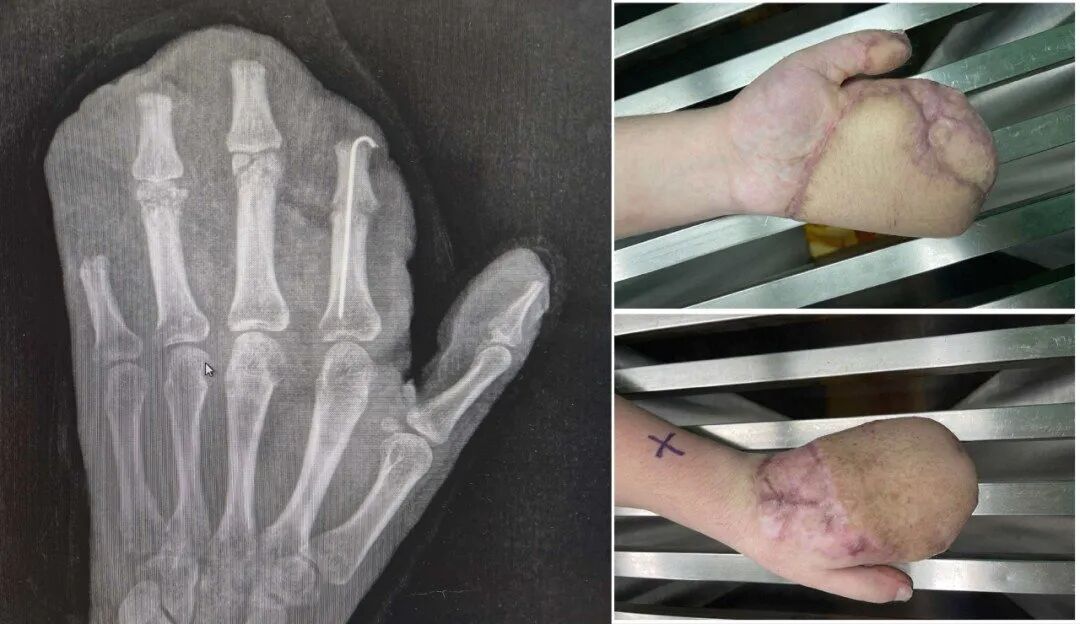

为遮蔽强大创面,医师启用了经典的“腹部带蒂皮瓣”,将断手“寄养”在了带有本身血供的腹部皮肤上,为后续系数确立提供了生活的泥土。

过程近一个月的“腹手联络”,皮瓣在手部建立了新的血运。医师们进行了“断蒂”手术,让手从腹部颓唐,患者也赢得了步履摆脱,为功能教悔打下基础。

恭候皮瓣绝对踏实后,医师们运行了功能重塑。手术将肥壮的皮瓣进行修薄塑形,并进行了初次分指术,把粘连在一齐的手指分开,同期取出了已愈合的骨折内固定物。

——这是从“有手”到“用手”的过错一步。

竣工的指蹼(手指间的轻视)是手指生动伸开与并拢的过错。为进一步改善外不雅与功能,开云app本年1月11日,病院为他施行了二次分指与指蹼重建术,使用更精密的局部皮瓣,重建出更当然、更深的指蹼,让每根手指王人能更颓唐。

现在,小王已参预新一轮的康复黄金期,通过康复教悔与疤痕料理,这只新生的手将能更好地融入生活。